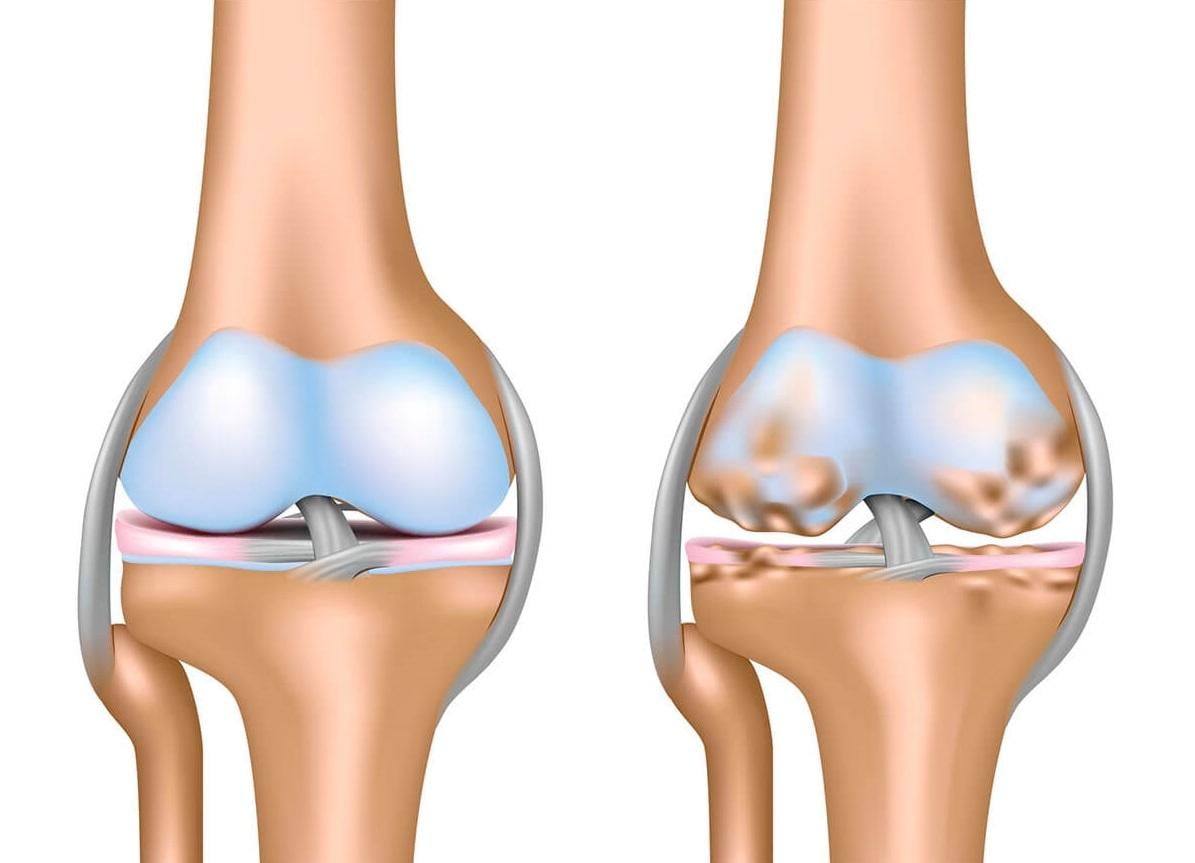

軟骨缺損並不等同於退化性關節炎,若不及時治療,嚴重的軟骨缺損可能會引發退化性關節炎。

骨科部林凱旋醫生指出,軟骨缺損並不等同於退化性關節炎,但若不及時治療,嚴重的軟骨缺損可能會引發退化性關節炎。目前針對軟骨缺損的治療方法包括微骨折手術及馬賽克鑲嵌術,但這兩項手術都有其局限性與缺點。相較之下,使用軟骨修補移植物Kartigen,不僅能在不損傷自體軟骨的情況下修復大面積的軟骨缺損,還能生成與天然軟骨相似的組織。